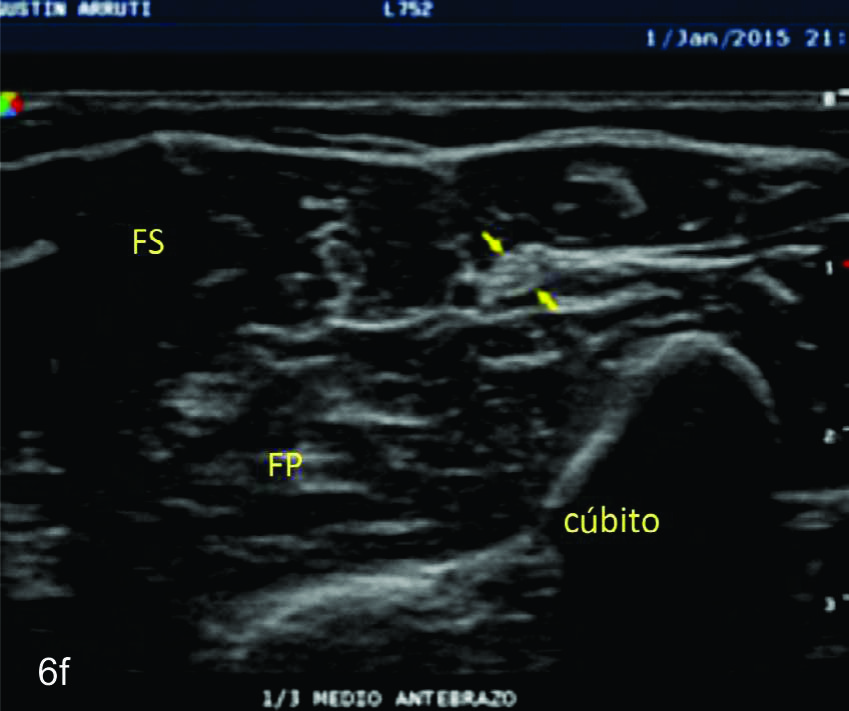

Figura 6

Nervio cubital

B- tercio medio del brazo,

C- tercio distal del brazo,

D- codo en canal epitrocleo-olecraneano,

E- codo- canal cubital,

F- tercio proximal antebrazo,

Serie de cortes axiales del nervio mediano desde su origen a nivel del hueco axilar hasta el sector distal del antebrazo previo a su ingreso al túnel del carpo. Se identifica el mismo señalado por flechas amarillas y con la palabra mediano. AA-arteria axilar, VA- vena axilar, AH- arteria humeral, VH- vena humeral, VB- vena basilar, AC- ateria cubital, VC- vena cubital, BA- músculo braquial anterior, PR- músculo pronador cuadrado, FS- músculo flexos superficial, FP- músculo flexor profundo, PC- músculo pronador cuadrado. A- axila, se identifica el nervio superfical a la arteria axilar, B- tercio medio del brazo en canal bicipital medial, lateral a la arteria humeral, C- codo, medial al tendón distal del bíceps braquial y a la arteria humeral luego de cruzarla, superficial al músculo braquial anterior, D-antebrazo sector cefálico, entre las dos cabezas del pronador redondo, E- tercio medio del antebrazo, entre los músculos flexor superficial y profundo F- tercio distal antebrazo, superficial al pronador cuadrado.